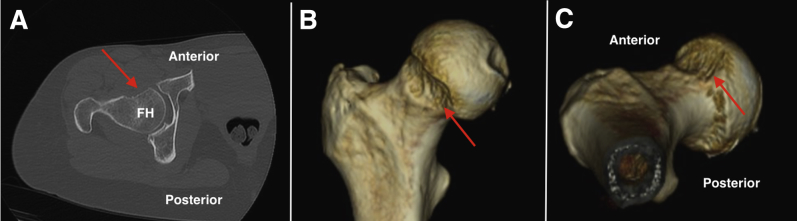

Fig 2.

(A) An axial computed tomography (CT) image of a right hip that has undergone an over-resection of a previous cam lesion. Three-dimensional coronal (B) and axial (C) CT reconstruction of the proximal femur further showing areas of cam excessive resection of the femoral head-neck junction. Areas of excessive resection are noted with red arrows. (FH, femoral head.)